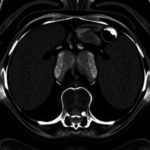

Одним из главных плюсов, которыми обладает современное узи брюшной полости, является высокая точность диагностики. Современные аппараты позволяют увидеть даже малейшие изменения в органах и тканях брюшной полости, что делает исследование максимально эффективным и информативным.

Высокочастотные датчики в современном узи брюшной полости имеют множество преимуществ. Они позволяют получать более точные и детальные изображения, что делает диагностику более эффективной и точной. Кроме того, высокочастотные датчики помогают выявлять более ранние стадии заболеваний, что в свою очередь увеличивает шансы на полное восстановление пациента.

Современные аппараты ультразвуковой диагностики имеют множество конструктивных особенностей, которые позволяют осуществлять точную и безопасную диагностику брюшной полости.